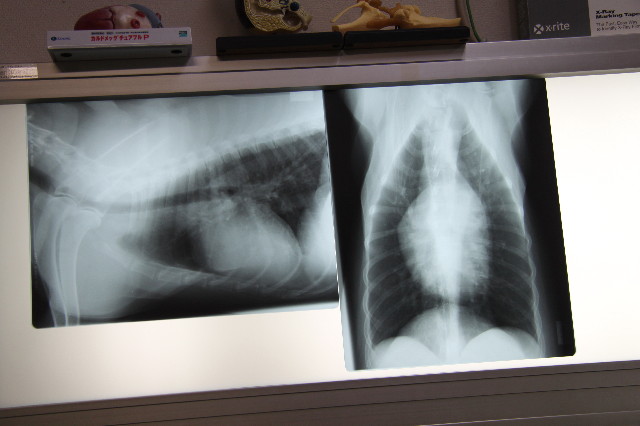

レントゲンとエコーを取ってもらったんだけど、肺があちこち石灰化してはいるけどそんなにひどくなし気管支もちゃんと写っているから大丈夫でしょうって。

(黒い大きな四角っぽい部分が肺で、肺の真ん中の白っぽいのが心臓)

肺のあちこちで白く粒々して見えるのが石灰化したところ。